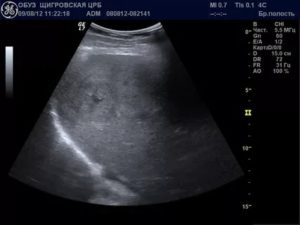

Очень часто в почках возникает нарушение оттока мочи, которое может показать ультразвуковой прибор. Выделяют несколько стадий гидронефроза:

- Расширение почечной лоханки, паренхима почки при этом не изменена.

- Расширение лоханки и чашечек, истончение паренхимы.

- Кистозное расширение лоханки и узкий ободок паренхимы.

- Паренхиму полностью не видно, она не функционирует, почка представляет собой «мешок» с расширенными чашечками.

Причины нарушения оттока могут быть разными: закупорка мочеточника конкрементом, сгустком крови, сдавление опухолью, беременной маткой и другие.